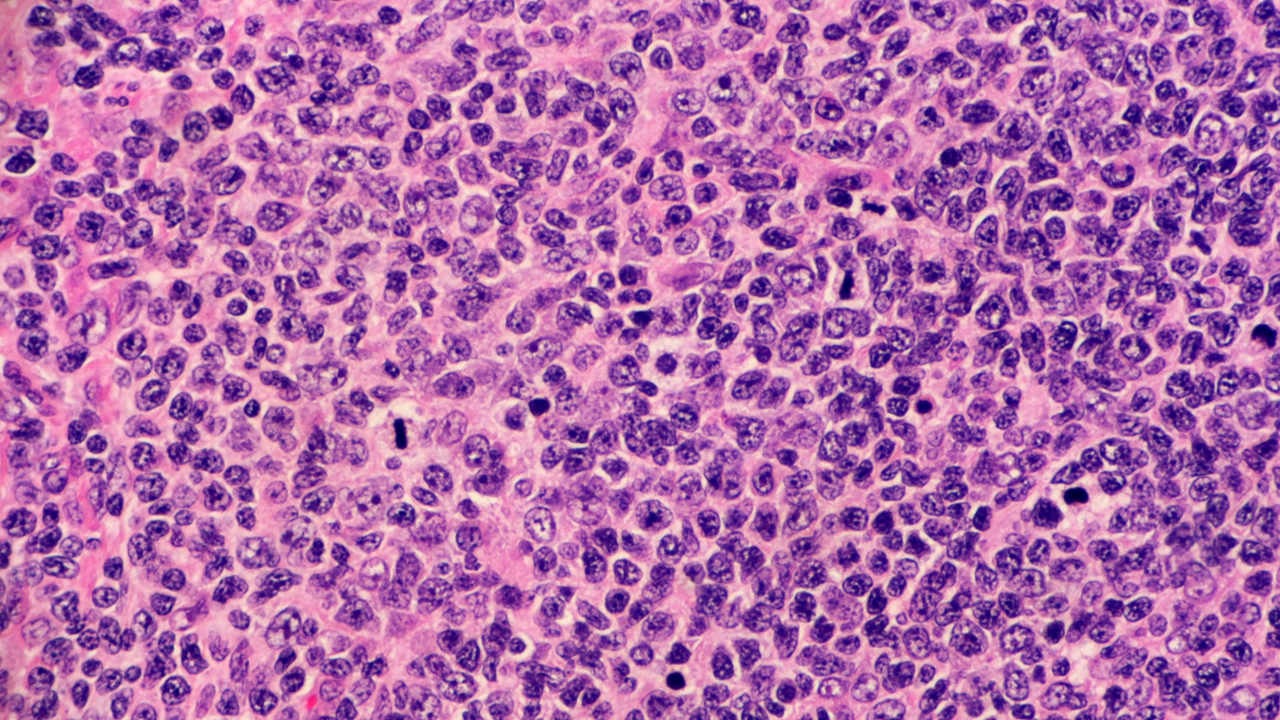

Incyte anunció los resultados positivos del estudio pivotal inMIND, un fase III, global, doble ciego, aleatorizado y controlado. El estudio evaluó la eficacia y seguridad de tafasitamab, un anticuerpo monoclonal humanizado modificado que va dirigido a CD19, en combinación con lenalidomida y rituximab, en pacientes con LF R/R de grado 1 a 3a o linfoma de la zona marginal nodal, esplénico o extranodal R/R. En el estudio participaron un total de 654 adultos (edad ≥18 años). Los hallazgos sugieren que esta combinación podría representar un nuevo enfoque en el tratamiento de esta forma común de linfoma no Hodgkin de crecimiento lento.